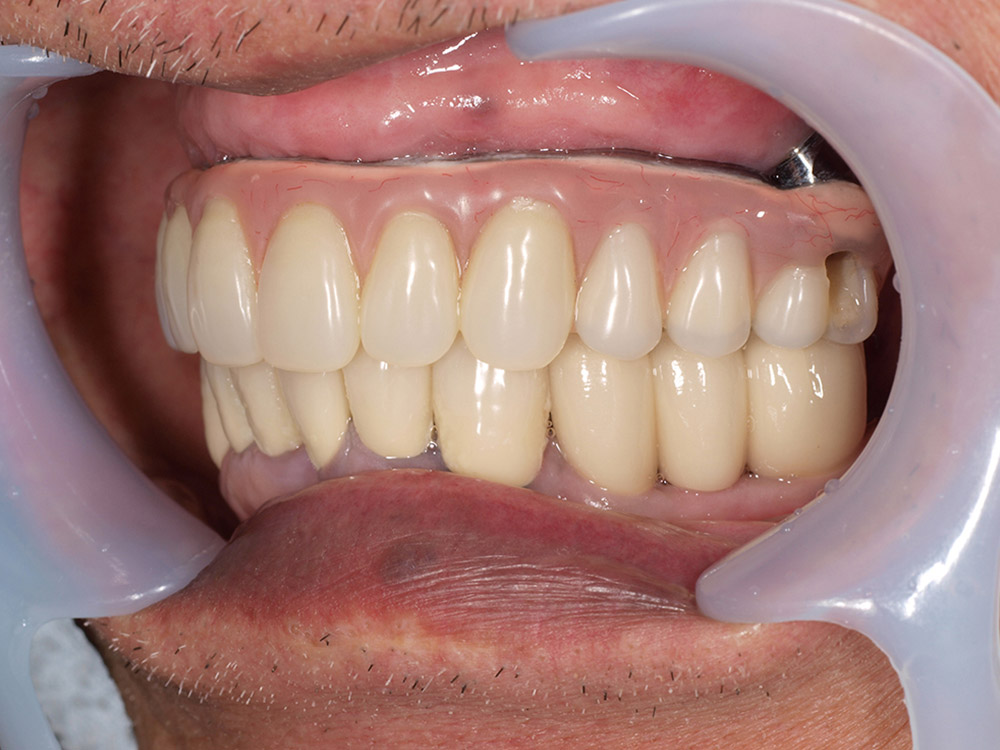

- 主訴

- 上顎入れ歯が辛い、下顎左右の歯が痛い、揺れる

- 処置内容

- 上顎6本(オールオン6) 下顎3本

- 治療費用

- 上顎:約350万円(税込)、下顎:約310万円(税込)仮歯まで5か月)

- 治療期間

- 上顎:1年(仮歯まで8か月)/約10回

下顎:8か月(仮歯まで5か月)/約7回

- リスク

- 上部構造物、仮歯の破折、術後の腫れ(3日)、人工歯根脱落リスクがあります